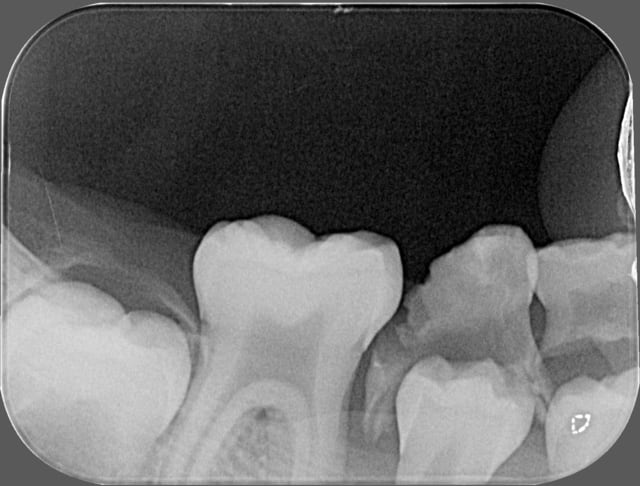

abcès important en regard de la 84, j'extrais ce jour la dent,mais comme je n'ai pas pu avoir une bonne rétro,je fais une pano,

est-ce qu'il y a une image au niveau de la 46 ?

problème au niveau de l'apex de 45 ?

en gros l'abcès (évolution en cellulite) peut-il être du à un problème sur 44 , 45 ou 46 ?

je pense vraiment que les lésions à l'apex de 44, 45 et 46 sont juste l'image de la formation des apexs et que cela n'a rien à voir avec une image infectieuse. Surtout, d'où serait venu les bactéries?

La 45 est bizarre, on dirait que la racine n'a quasiment pas été formée alors qu'elle n'est pas si profonde.

La radioclarté autour de 45 est douteuse.

Franchement, je ne vois pas en quoi 44 45 46 pourraient être mises en causes et l'apparence de radioclarté me semble plus liée à une ligne dense continue qui se prolonge en région symphysaire et qui s'apparente à un artéfact cinétique de la pano.

Ce serait quand même surprenant que sur les 2 panos il y ait eu un artéfact exactement au même endroit, et à l'endroit où on suspecte quelque chose.

il semble que l'absence de formation radiculaire de la 45 peut être due à la perte précoce de la 85

La 85 était très moche, c'est la porte d'entrée la plus évidente, qui a dû perturber l'évolution de 45.

quelques idéees à mon amha!je pense que le problème vient des apex de la 46!!!

J'ai eu une patiente de 14 ans avec un genre de foyer/kyste

aux apex d'une 47 parfaitement vivante.J'ai demandé un avis d'une endodontiste exclusive qui m'a confirmé un kyste apicale du sans doute à une évolution non logique lors de l'apexification(peut etre évolution de la gaine D'Hetwig non conforme)Résultat curetage

La cellulite se transmet au travers de la joue à partir de 46

je ne vois pas la 84 responsable ni la 44 et 45 en évolution